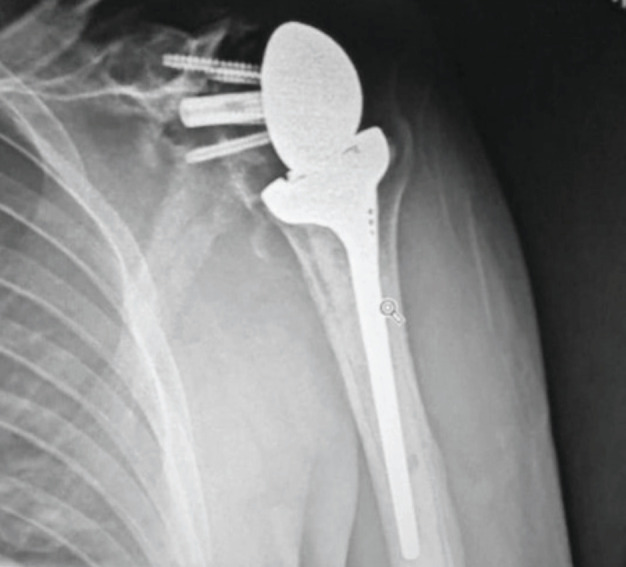

Abstract Image

Results: A total of 32 patients were identified with a mean age of 67.64 years and the most common cause of revision was a combination of bone and soft tissue failure (39.3%). All patients (n=8) with hemiarthroplasty had rotator cuff deficiency while patients with resurfacing had both rotator cuff failure and bony erosion. Four patients needed a proximal humeral osteotomy and six patients needed allograft reconstruction of the glenoid for bone loss. Twenty-one shoulders were revised to reverse total shoulder arthroplasty (TSA), 2 to anatomical TSA and 5 were left with cement spacer in situ. Mean duration of follow-up was 41.6 months. Mean OSS at the last follow-up was 26.88 with statistically significant improvement in ROM. There was no statistical difference in clinical outcomes (p>0.05) based on the type of primary prosthesis or cause of revision. A total of 70% patients were pain free. Patients with infection had inferior outcomes with a mean OSS of 17.